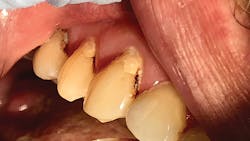

We use SDF in our office as an alternate treatment option for medically challenged patients and older adults. As our heavily restored older patients become more restricted in their ability to perform daily hygiene routines, such as brushing teeth and flossing, we start to see more marginal and root surface caries. The cause of this can be twofold: lack of proper plaque removal and poor diet. When interviewing patients in this age group or their caregivers, we find patients tend to experience dry mouth and often find relief from sipping on sugary beverages or sucking on hard, sugary candies. In a dry mouth, these habits accelerate tooth decay. Compromised medical situations often prevent patients from undergoing dental treatment.

As dental providers, it is our responsibility to educate patients and their caregivers and provide treatment options. For a patient who is in the last stages of dementia, it is neither ethically nor morally appropriate to put them through extensive restorative procedures or extractions. In our office, we place SDF at the initial diagnosis of decay after removing food debris and plaque, and then we reapply it at subsequent appointments. If the caregiver requests, we can follow up with treatment at the assisted living facility. SDF shows success with annual applications, but in our practice, we have seen greater benefits if SDF is reapplied at six-month intervals during the first two years. We attribute this to the difference in home-care plaque removal, habits, and diet, which are often uncontrolled in real-life situations, as compared to clinical trials.